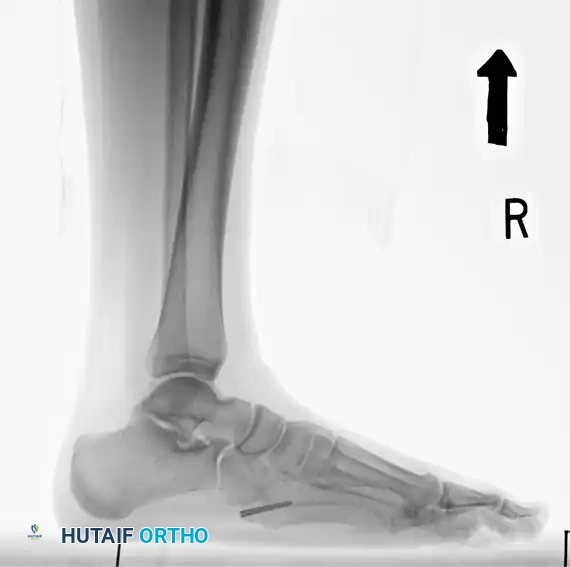

Standard weight-bearing anteroposterior (AP), lateral, and oblique radiographs of the foot are mandatory. The oblique view is particularly useful for profiling the fracture line at the metaphyseal-diaphyseal junction.

- Verify final screw placement, fracture reduction, and compression with orthogonal radiographs.